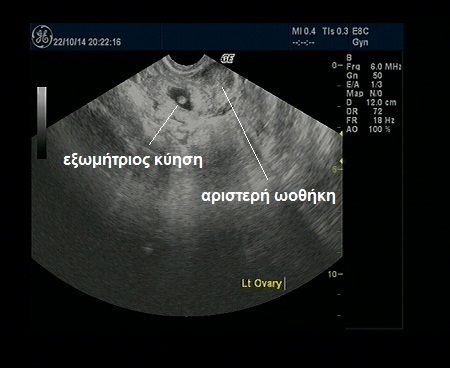

Με τον υπερηχογραφικό έλεγχο είναι όμως δυνατόν να εντοπίσουμε το κύημα εκτός μήτρας, αν η κύηση έχει προχωρήσει και αυτό είναι αρκετά μεγάλο. Έτσι στην περίπτωση αυτή δεν μιλάμε πια για υποψία αλλά για βεβαιότητα ύπαρξης εξωμήτριου κύησης. Αυτό φαίνεται στην παρακάτω φωτογραφία από έναν υπερηχογραφικό έλεγχο, που εκτελέσαμε στο ιατρείο μας.